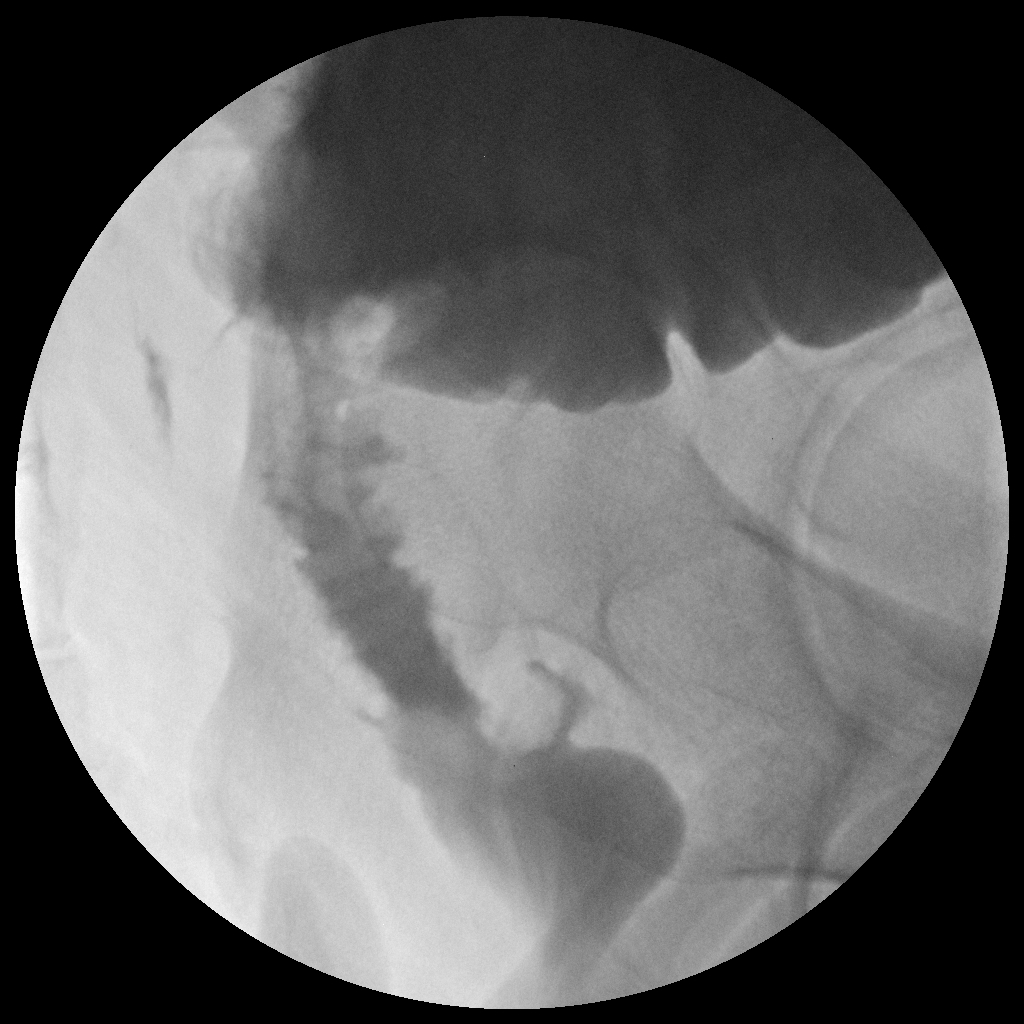

C-reactive protein and procalcitonin and other acute-phase reactant biomarkers have been studied in an effort to make an early AL diagnosis. Although there is no consensus, these biomarkers have reasonably good negative predictive value but lack positive predictive value.[10] Contrast enema and computed tomography (CT) are the most useful confirmatory diagnostic radiologic studies (Figure 1 and Figure 2). However, the diagnosis of AL at imaging is not always obvious, and there is little consensus on confirmatory findings.[1] Early postoperative CT may show an obvious leak with pneumoperitoneum or extraluminal extravasation of oral or rectal contrast. However, CT also may show rim-enhancing fluid collections or specks of free air that are equivocal for leaks.[1] Compared with contrast enema, CT has the added advantage of assessing the anastomotic defect circumferentially, detecting a contained leak, an abscess where there is no extravasation of contrast, other intra-abdominal fluid collections, an associated small bowel obstruction, and/or unrecognized bowel injuries. CT is most diagnostic when performed with intravenous, oral, and rectal contrast. One study showed that CT results with rectal contrast were associated with significantly more patients with contrast at the anastomosis compared with CT scans without rectal contrast (81.7% vs. 26.0%, p < 0.001). CT results with rectal contrast are also associated with fewer false–negative scans (4.6% vs. 18.0%, p = 0.004), less mortality (4.6% vs. 16.0%, p = 0.006), and less failure to rescue (7.9% vs. 19.5%, p = 0.048).[11] For patients with a distal rectal anastomosis, the rectal catheter for delivering contrast is often positioned by the surgeon to minimize trauma and to optimize the flow of contrast through the anastomosis. It is also an opportunity to gently palpate the anastomosis for defects. Failure to diagnose an AL may result in a chronic sinus tract and cavity with long-term sepsis or need for permanent stoma.

Figure 2. CT Scan Showing Fluid Collection due to Anastomotic Leak

Descriptive text is not available for this image